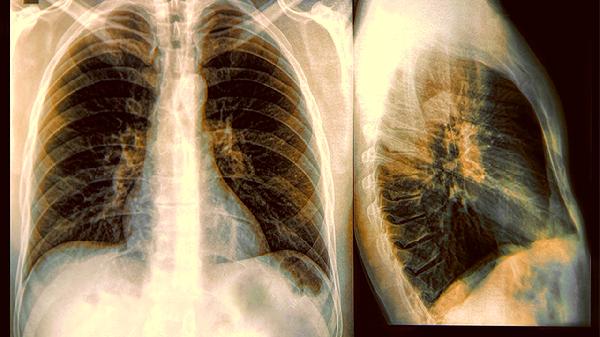

嘴上叼着香烟吞云吐雾的姿势,在影视剧里可能很"酷",但现实中那些飘散的烟雾正悄然侵蚀着肺泡。当体检报告单上出现"肺结节"三个字时,很多人第一反应就是:"完了,该戒烟了!"可你知道吗?点燃烟草只是打开潘多拉魔盒的钥匙,真正释放致癌恶魔的另有其人。

烟草中确实含有78种明确致癌物,但流行病学数据显示,从不吸烟人群的肺癌发病率近二十年上升了43%。就像烧烤时冒烟的炭块,焦油和尼古丁虽然是主要污染源,但助燃的"隐形炭块"才是持续放毒的关键。